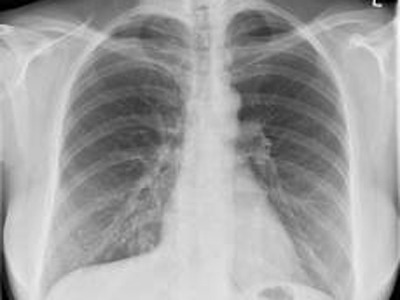

Elk van de vijf elementen (Vuur, Aarde, Metaal, Water, Hout) is herkenbaar door verschillende kenmerken. Metaal is … seizoen, temperatuur, smaak, opening, paleis, opslag, emotie, vorm. Metaal is … herfst, droogte, scherp, neus, dikke darm, longen, vertrouwen, kantoor, ovaal.